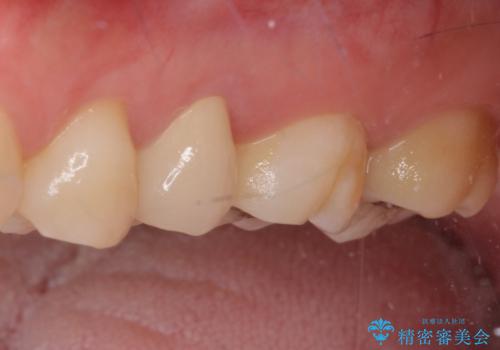

2歯ともに根管治療を行い、その後はオールセラミッククラウンにて補綴治療を行うこととしました。

来院時には食事が取れないほどの痛みを訴えていらっしゃいましたが、処置後からは痛みが軽減され、食事もいつも通りに取れるようになりました。